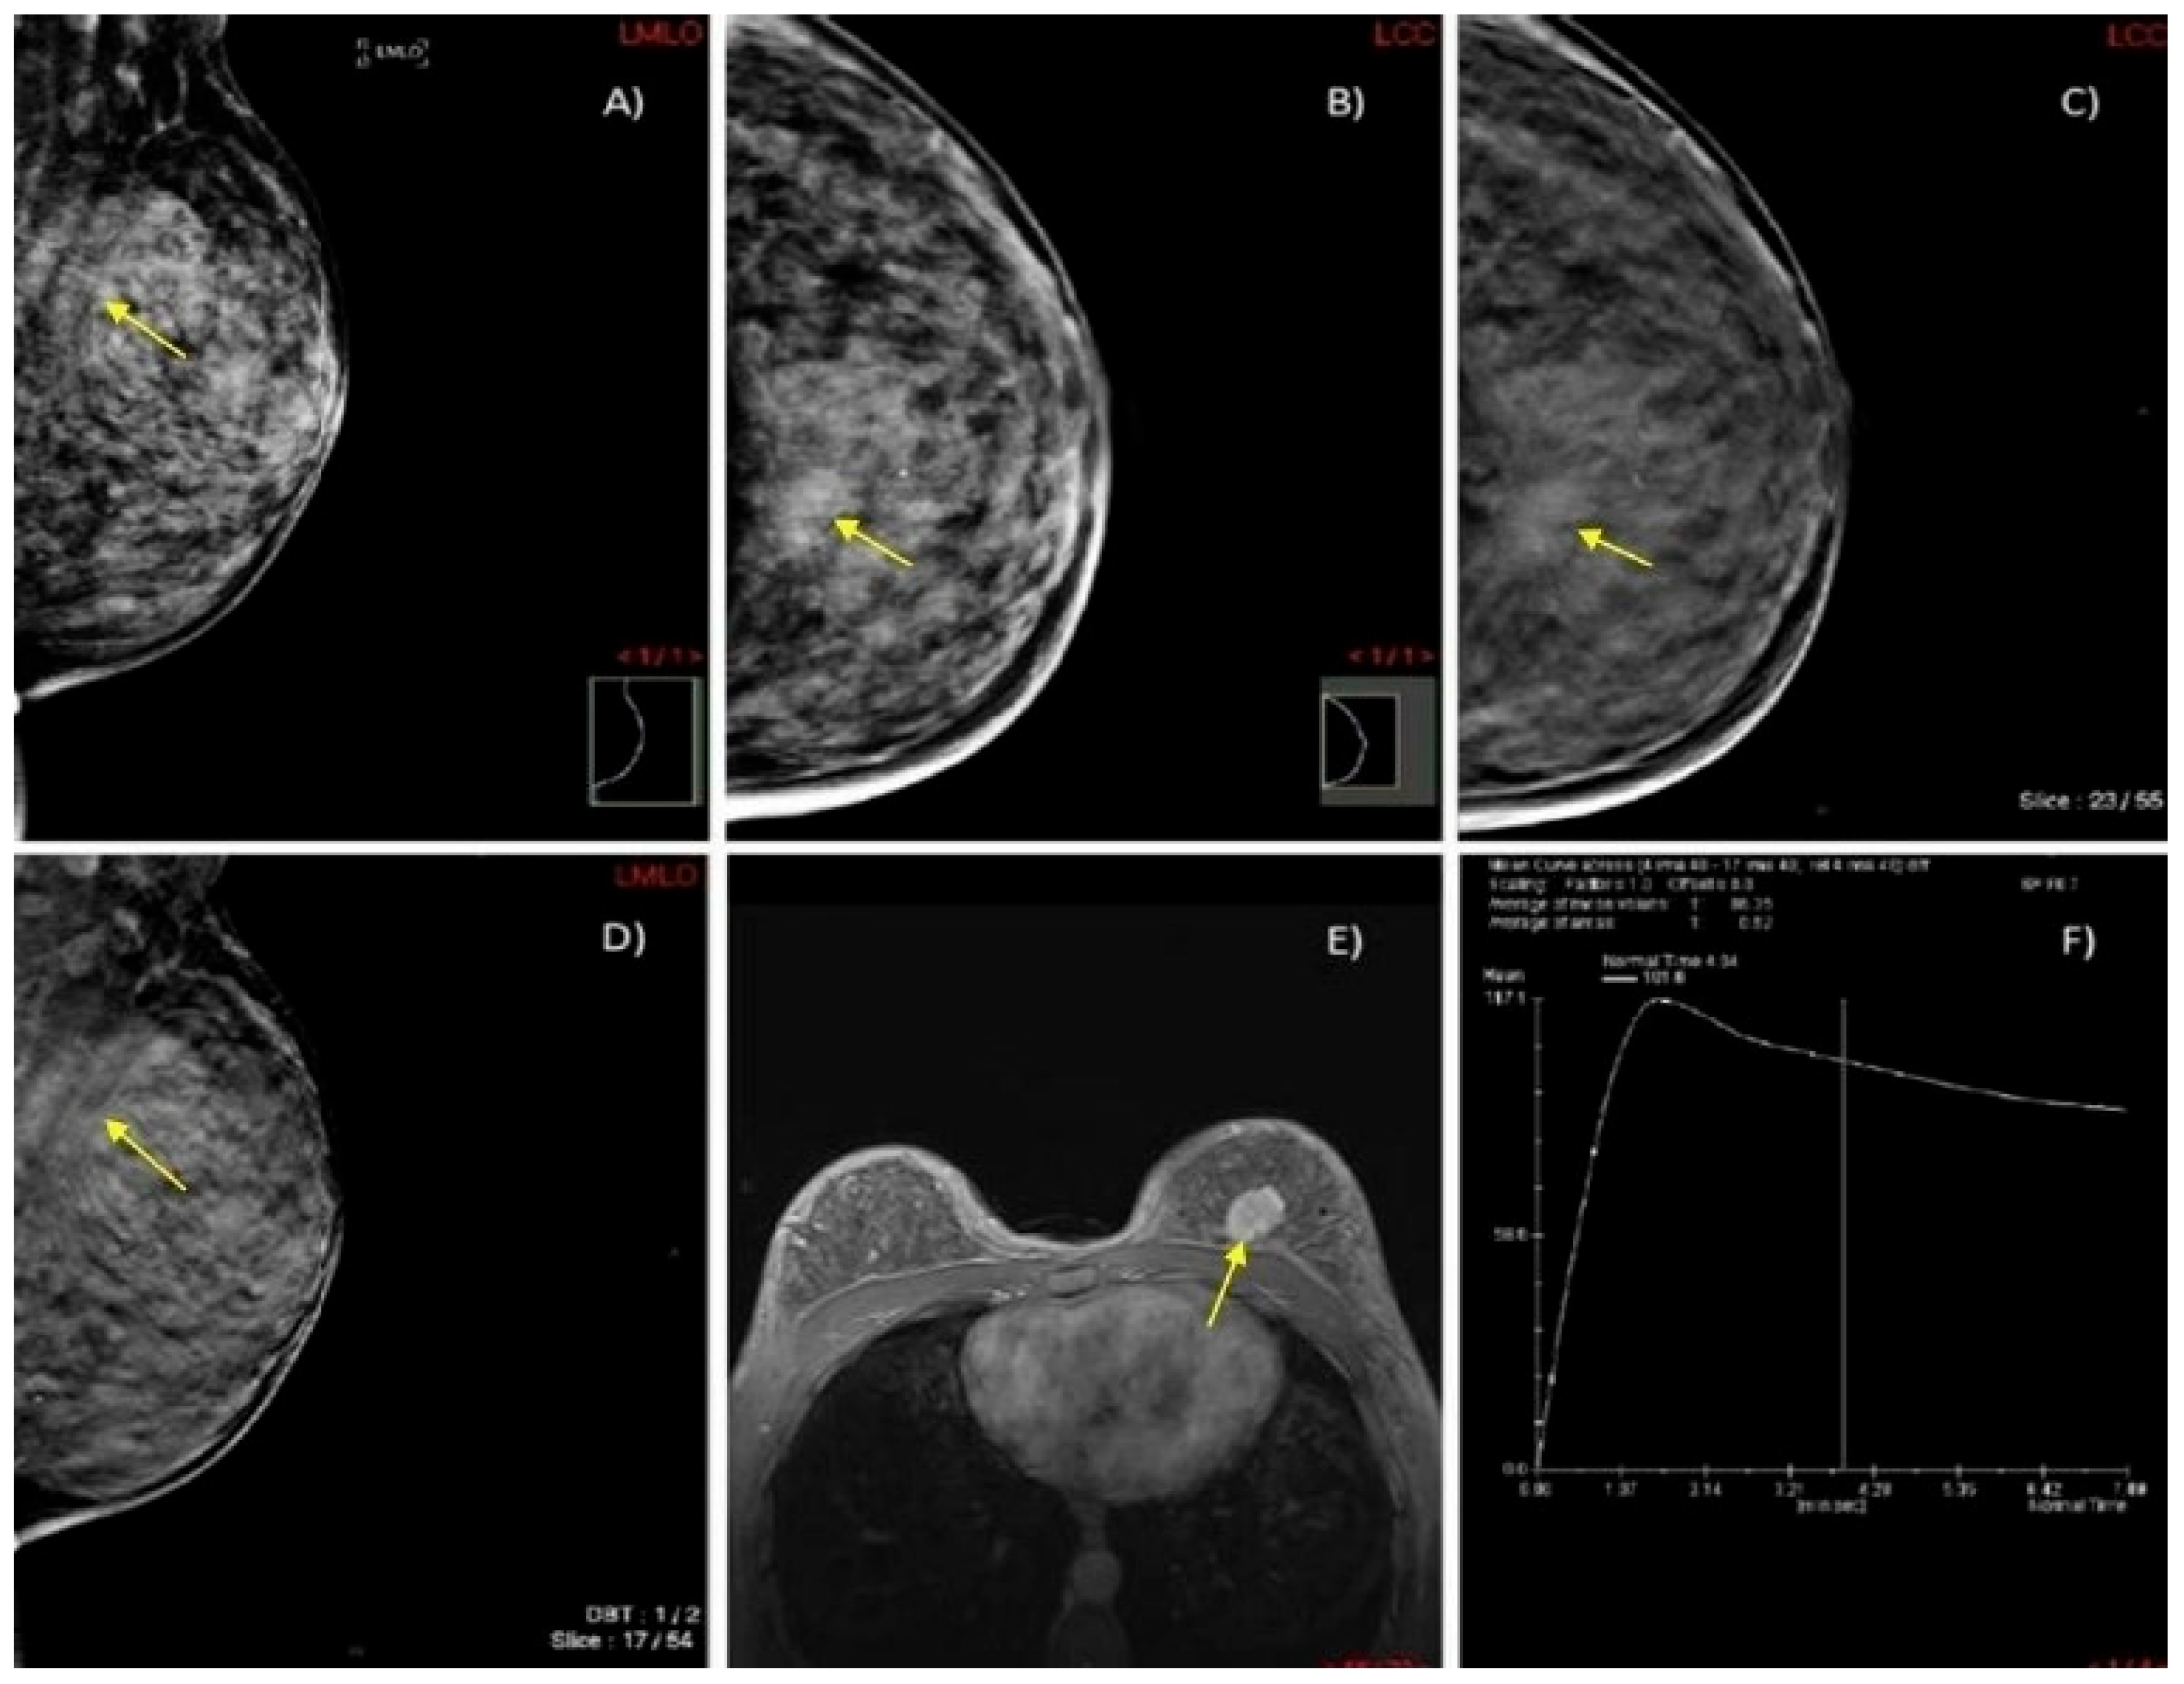

We present two illustrative cases from our female patient cohort, each with HPE-confirmed diagnosis in dense breasts. These lesions were identified using MRI, DM, and DBT, as demonstrated in Figure 5 and Figure 6.

Figure 6.

A case of a 45-year-old woman with extremely dense breasts (ACR category D) and HPE-confirmed invasive ductal cancer in the left breast. (A,B) DM in MLO and CC projections shows an architectural distortion in the upper inner quadrant of the left breast (yellow arrow). (C,D) DBT in MLO and CC projections illustrates a spiculate mass in the upper inner quadrant of the left breast (yellow arrow). (E) Axial 3D T1-weighted FLASH fat-suppressed (FS) MR image demonstrates an extensive post-contrast hyperintense lesion in the prepectoral space of the left breast (yellow arrow). (F) MRI dynamic contrast enhancement curve type III (“wash out” curve).